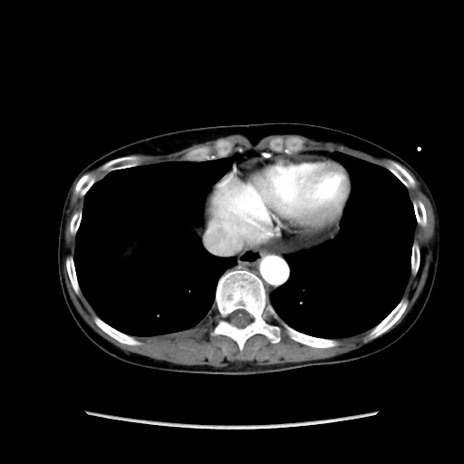

症例32(横断像)

【症例】40歳代 女性

【主訴】上腹部痛、嘔気・嘔吐

【現病歴】約9時間前頃から急に上腹部痛、嘔気、嘔吐が出現。改善しないため救急要請。

【既往歴】子宮頚癌(広汎子宮全摘術、放射線療法)、腸閉塞

【身体所見】腹部:平坦、軟、腸雑音亢進、上腹部を中心に腹部全体に圧痛あり。

【データ】WBC 8400、CRP 0.03